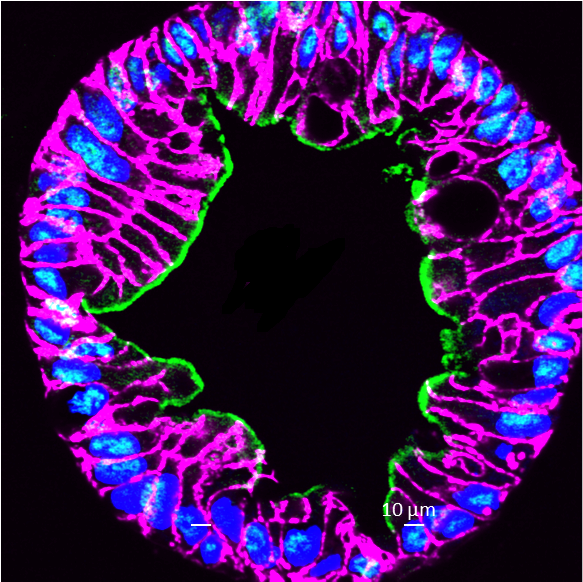

Our lab studies several facets of GI infection by two enteric viruses (#rotavirus and #norovirus) utilizing stem-cell derived organoids/ enteroids.